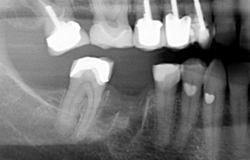

| Before | After |

Cantilever Bridge – This is a bridge with one false tooth or ‘pontic’ which is attached to one crown ‘the abutment’

Fixed- Fixed Bridge – Generally consists of three crowns joined together, one at each end which cover your natural teeth and a crown in the middle which replaces your missing tooth.- Some bridges may actually be four, five or even more crowns joined together, designed to replace more than one of your missing teeth

Adhesive Bridge – This bridge has a false tooth (the pontic) to which a metal or tooth coloured ‘wing’ is attached to a natural tooth on either side of the missing tooth. This type of bridge can have one or two wings